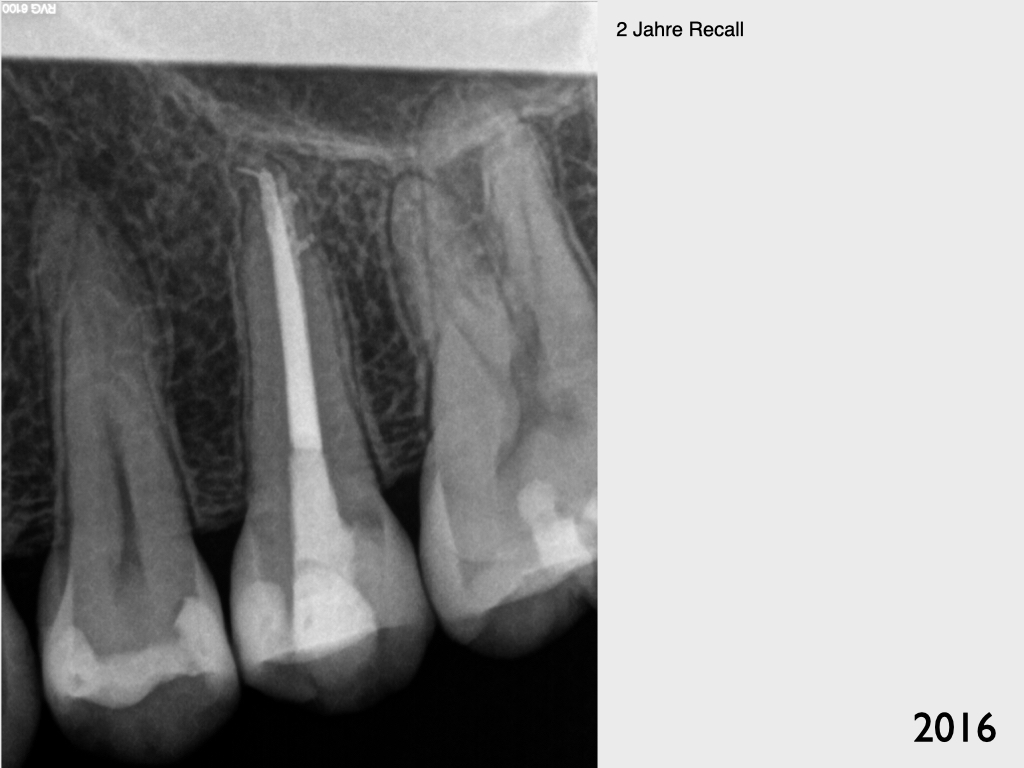

Recall 7 Jahre